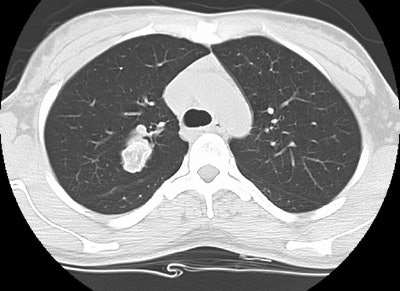

Pulmonary Hamartoma

The patient shown in the case below was referred for evaluation of a right upper lobe mass. The CT scan demonstrates a large mass in the right upper lobe that contained macroscopic fat consistent with a hamartoma. Lung windows demonstrated the lesion to be endobronchial and this was confirmed at surgical resection. (Click images to enlarge)